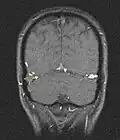

Wegen dieser Schwierigkeiten wird bei entsprechendem Verdacht frühzeitig eine Schnittbilddiagnostik des Schädels empfohlen. In der Computertomographie oder Kernspintomographie sind Infarktzonen und Blutungen erkennbar, die nicht den bekannten arteriellen Versorgungsgebieten entsprechen. In der nativen Computertomographie (ohne Kontrastmittel) kann sich das Gerinnsel im Sinus hell, also dichter als das umliegende Gewebe (hyperdens), darstellen. Mit Kontrastmittel lassen sich sowohl in der Computertomographie wie auch in der Kernspintomographie die Gerinnsel direkt als Aussparung in den ansonsten kontrastierten Sinus meist gut erkennen. Die Diagnose kann gelegentlich schon im CT gestellt werden. In der Regel ist aber eine CT-Angiographie oder Kernspintomographie erforderlich. Mittel der Wahl zur Diagnostik von Venen- und Sinusthrombosen ist die Kernspintomographie, sie ist aber nicht immer verfügbar. Die Kernspintomographie sollte auch suszeptibilitätsgewichtete Bilder und eine Time-of-flight-Angiographie enthalten, um alle Thrombosen zu erfassen.[23] Die interventionelle Angiografie mit einem Katheter kommt nur noch in Ausnahmefällen in Betracht und spielt im deutschsprachigen Raum fast keine Rolle mehr.[2] Bei Neugeborenen wird die Ultraschalluntersuchung des Gehirns über die Fontanelle vorgezogen.[5]

- Bildgebung bei zerebralen Thrombosen (zum Vergrößern Bilder anklicken)

-

-

Axiales SWI-Bild der scheitelnahen Duravenen. Die Thrombose ist im rechten Bild blau hervorgehoben.

Axiales SWI-Bild der scheitelnahen Duravenen. Die Thrombose ist im rechten Bild blau hervorgehoben. -

-

Andere SVT (gelbes Kreuz), Einzelschicht aus einer MR-Angiographie.

Andere SVT (gelbes Kreuz), Einzelschicht aus einer MR-Angiographie. -

-

CT ohne Kontrastmittel (links), und der gleiche Fall im MR mit Kontrastmittel. Thrombus durch roten Pfeil gekennzeichnet.

CT ohne Kontrastmittel (links), und der gleiche Fall im MR mit Kontrastmittel. Thrombus durch roten Pfeil gekennzeichnet.